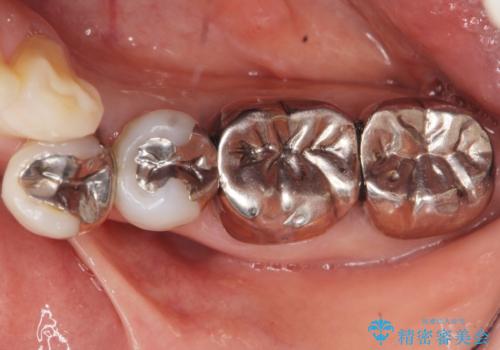

- 右下の4、5番目の歯の間に物がよく詰まる、また冷たいものも時折しみるので診て欲しいと来院された方の症例です。

右下4番目の歯は虫歯除去後、セラミックインレーにて修復処置を行いました。

右下5番目の歯はファイバーコアによって支台歯の築造を行い、オールセラミッククラウンにて補綴処置を行いました。

右下5の再根管治療および他歯の治療は特に症状を認めず、また患者様が御希望されなかったため行いませんでした。

- ¥100,000(オールセラミッククラウン(st))、¥70,000(セラミックインレー)、¥20,000(ファイバーコア)費用は治療当時の料金となります